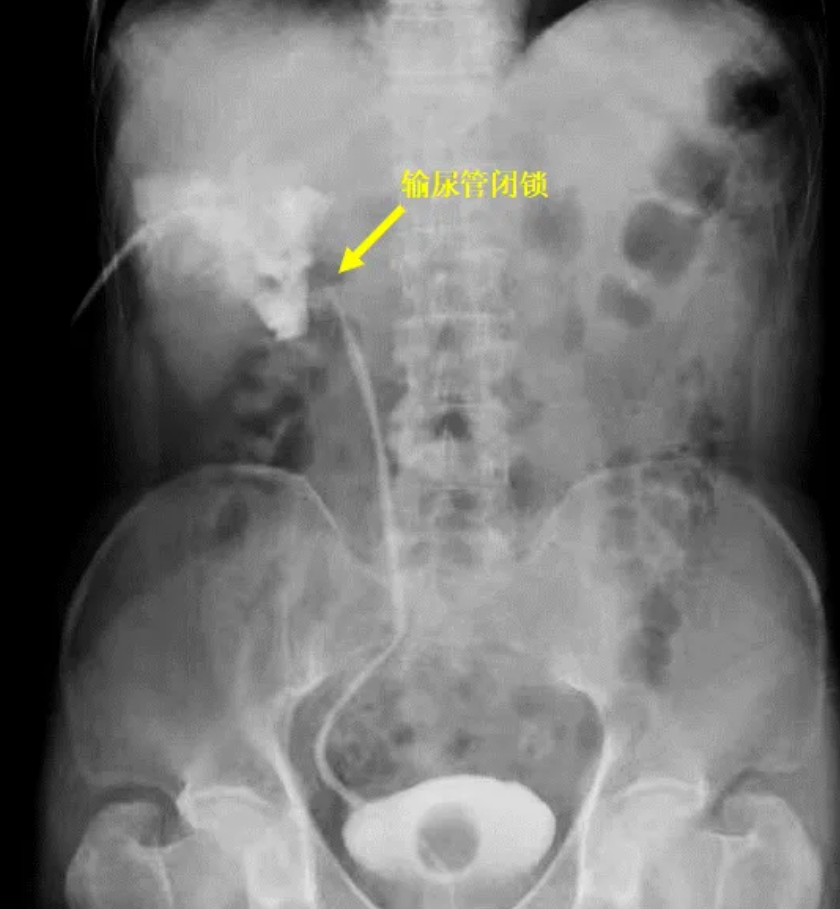

After the operation, the hydronephrosis did not improve, so Mr. Li underwent nephrostomy at the local hospital. A post-fistulization angiogram showed complete obliteration of the ureteral stricture at the renal hilum.